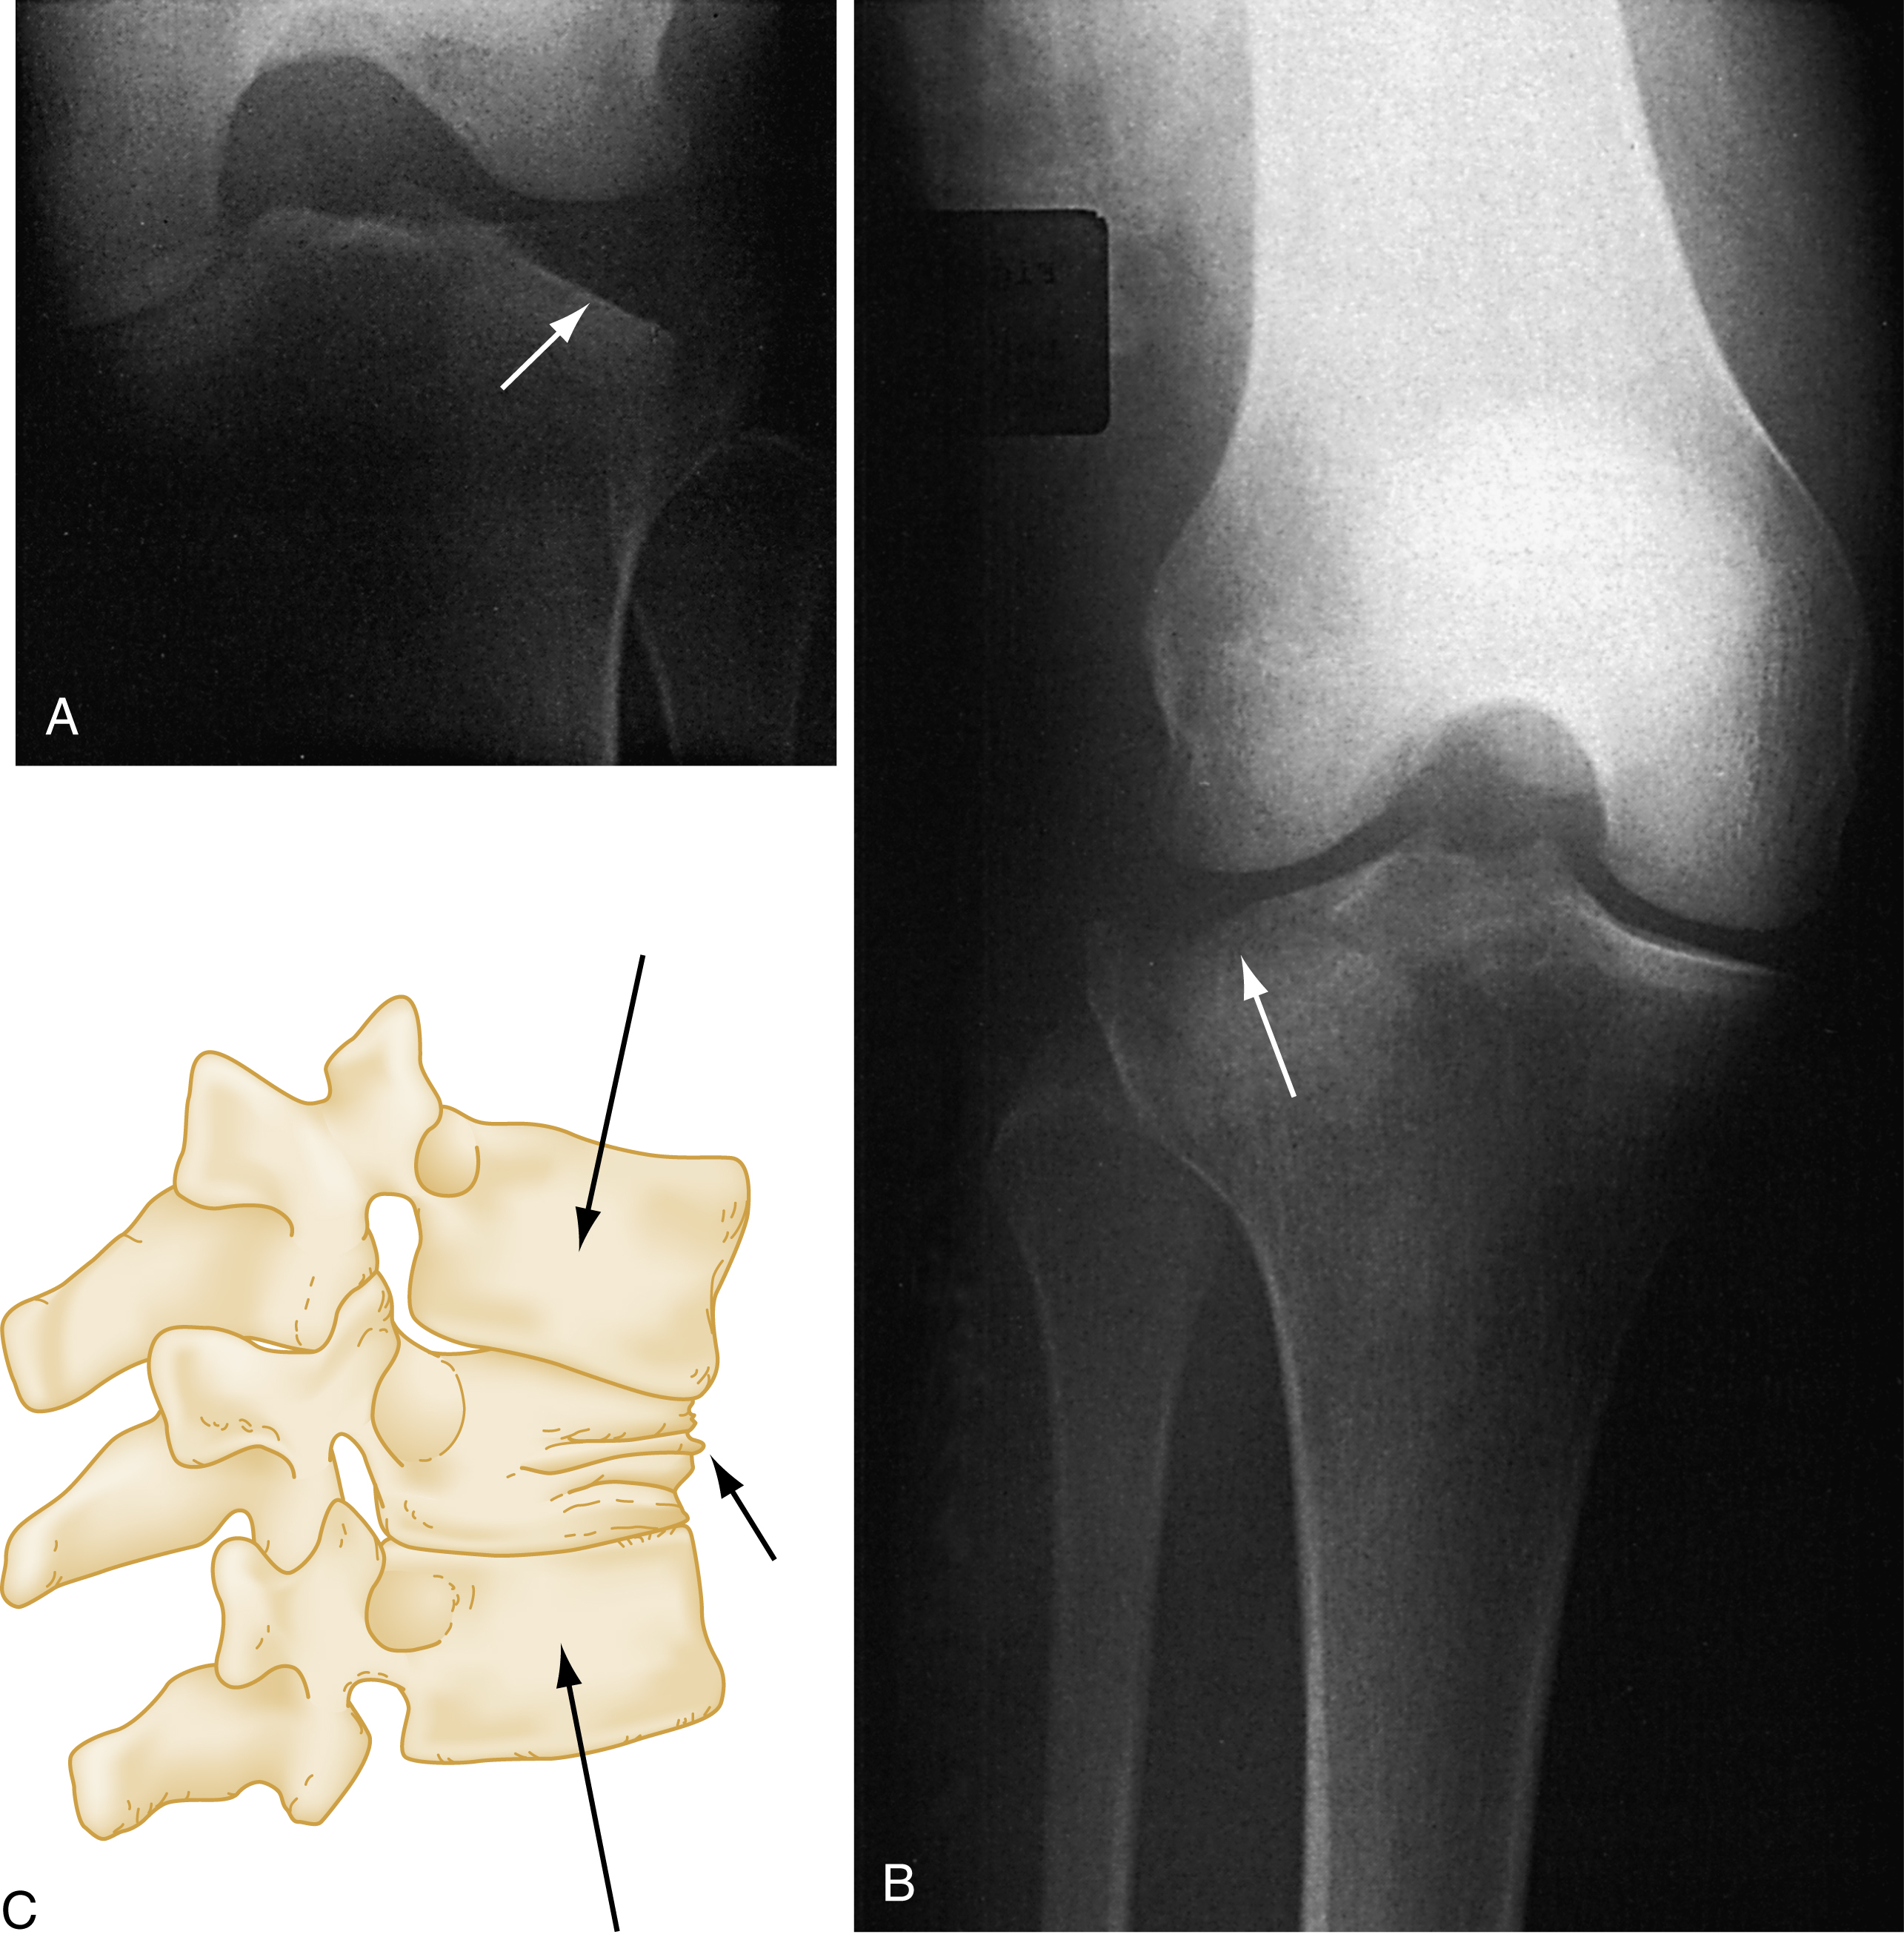

An additional modifier describes the direction of the fracture line in relation to the long axis of the bone in question. A transverse fracture occurs at a right angle to the long axis of the bone ( Fig. 41.1A ) whereas an oblique fracture runs oblique to the long axis of the bone (see Fig. 41.1B ). A spiral fracture results from a rotational force, a torque, and encircles the shaft of a long bone in a spiral fashion (see Fig. 41C ). The terms oblique and spiral are sometimes confused but can be important since the latter may have significance when child abuse is being considered as a mechanism of injury. A fracture with more than two fragments is termed comminuted (see Fig. 41.1D ).

Types of Fractures.

(A) Transverse. (B) Oblique. (C) Spiral. (D) Comminuted.

The term avulsion fracture refers to a bone fragment that is pulled away from its normal position by the forceful contraction of a muscle ( Fig. 41.5A ) or the resistance of a tendon or ligament to a force in the opposite direction (see Fig. 41.5B ). The term impaction refers to the forceful collapse of one fragment of bone into or onto another. In the proximal humerus, this collapse typically occurs in a telescoping manner, particularly in older patients, whose bones are osteoporotic and brittle. In the tibial plateau, impaction occurs frequently in the form of a depression ( Fig. 41.6A and B ) and, in the vertebral bodies, impaction frequently occurs in the form of compression resulting in a significant loss of bone height in some cases (see Fig. 41.6C ).

Avulsion Fractures.

(A) Musculotendinous avulsions of small bone fragments from the head of the humerus (arrows) . (B) Extensor tendon avulsion of bone from the base of the middle phalanx (arrow) .

(A and B) Tibial plateau fracture. (C) Vertebral body compression fracture (arrows) .